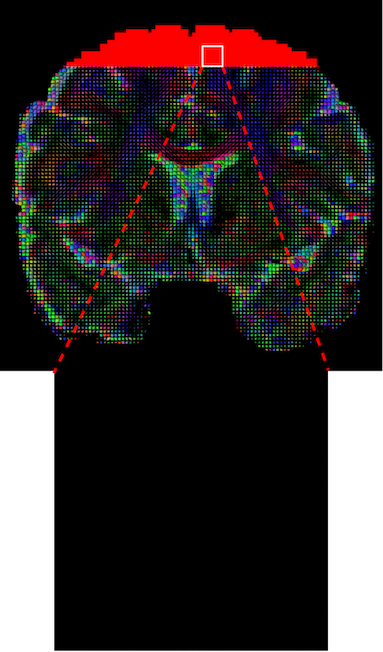

However, the acquisition can be sub-optimal due to clinical imaging constraints, such as acquisition time or patient movement during the MRI session. Unlike the structural imaging that usually requires a single acquisition, DWI requires multiple sequences with varying gradient pulses. The larger the number of gradient pulses needed in the scanning phase, the higher the angular resolution of the output DWI will have, which leads to a better representation of microstructure at the expense of a longer scanning time and higher cost. As a trade-off in clinical imaging practice, the field of view (FOV) for each subject might be reduced due to time and cost constraints, thus often resulting in missing slices from the superior part of the brain (this scenario is illustrated in Figure 2). Another common scenario is the unwanted disruption of the images and signal caused by different types of artifacts and noise including motion, susceptibility distortions, gradient non-linearity and eddy currents. A typical pipeline for DWI usually includes correction algorithms for these perturbations, however, even those methods can sometimes fail on particular cases leading to their exclusion from the study in real world scenarios. All these factors lead to disrupted DTIs and cascading errors as a result. For example, scalar metrics will be affected at the terminal points of the frontal and parietal lobes if the top part of the brain is cropped [10] and as mentioned, these subjects would fail quality control and be rejected for any further use [11]. Hence a solution for the problems listed above is necessary to obtain consistent and spatially-aware scalar metrics from disrupted DTIs for clinical studies without discarding valuable scans. Inspired by inpainting research, the solution we propose in this work is to reframe the problem as the inpainting of the disrupted regions in DTI volumes.

Although GAN-based methods can achieve satisfying results on natural images, the original implementation and its variations have limitations on their training stability due to the introduction of complex auxiliary architectures and their corresponding unstable losses that can lead to mode collapse [28, 29]. This problem becomes amplified when applied to 3D medical images due to the increased complexity and dimensionality. To this end, we propose Tensor-Wise Brain-Aware Gate (TW-BAG) Network, which is specifically designed for inpainting of missing slices in DTI images111The repository for this work is available at: https://mri-synthesis.github.io. The overall framework of TW-BAG Network is shown in Figure 2. To the best of our knowledge, TW-BAG is the first work that inpaints the cropped regions directly on DTI volumes, rather than the raw DWI sequence. Our experimental results show that TW-BAG is able to obtain satisfactory inpainting results in terms of computer vision metrics and from a clinical perspective. Extensive analysis has also been conducted on the efficiency of the model by feeding different percentages of valid brain training regions into the network to explore how much global brain information can help to reconstruct the missing slices and recover quantitative clinical information.

The visualization of inpainted results (showing the whole diffusion tensor for each voxel) generated from different models are demonstrated in Figure 3, where the tensor is represented in RGB coding that colours red, green and blue represent diffusion in the x, y, and z axes respectively. One typical example of reconstruction in the disrupted ROIs has been zoomed for visualization. Compared to the ground truth, TW-BAG is able to generate more distinct orientations following the original distribution and intensity across sagittal, coronal and axial views, which could demonstrate water diffusivity (denoted by eigenvalues of tensor model) more accurately. As indicated in Figure 4, the boundaries and textures of the FA map for TW-BAG are less blurry than the other competing models, validating the effectiveness of TW-BAG from a neuroscience perspective.